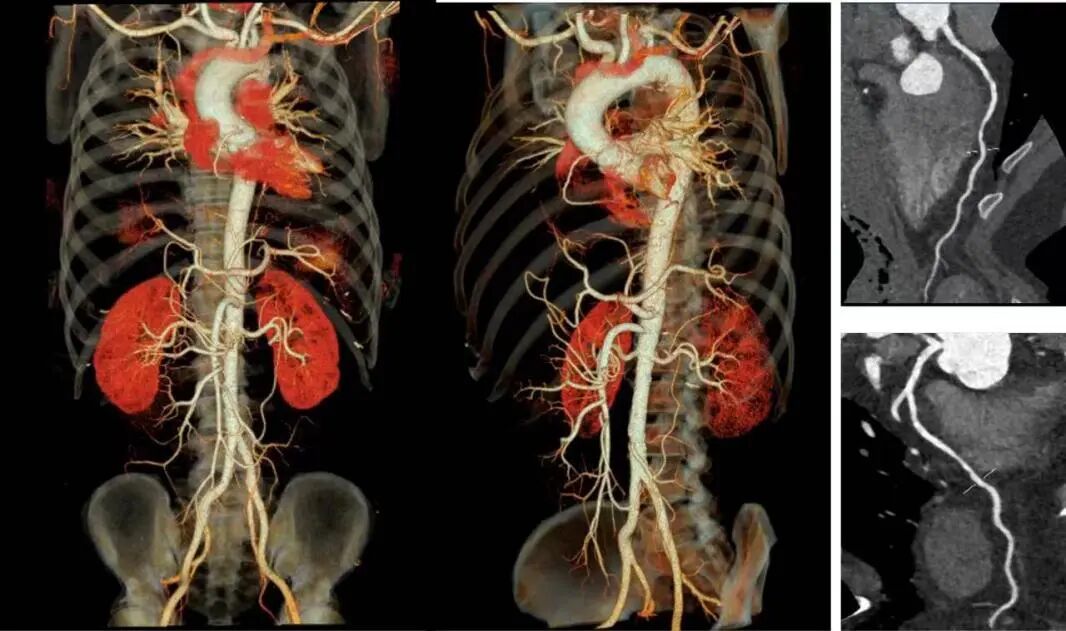

更全面——一站式多部位掃描

設(shè)備擁有16cm寬體等焦寶石探測器,是目前業(yè)內(nèi)最寬探測器,可一次性實現(xiàn)多血管或多器官聯(lián)合掃描。該CT獨有的自由組合一站式聯(lián)合掃描技術(shù),實現(xiàn)不同掃描模式的快速切換,患者只需注射1次造影劑即可快速完成全方位聯(lián)合掃描,如冠脈CTA+頭頸CTA,冠脈CTA+主動脈全程CTA,胸痛三聯(lián)(冠脈CTA+肺動脈CTA+主動脈全程CTA),大幅提升胸痛三聯(lián)征、心腦血管上下肢及胸腹血管病變的檢出率,為讓患者得到及時科學(xué)有效的診療提供了強有力的技術(shù)保障。